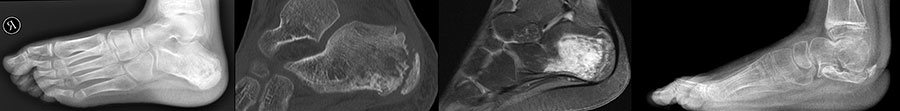

Juvenile Knochenzyste

Die juvenile Knochenzyste (Syn. Solitäre Knochenzyste) findet sich am Fuß fast ausschließlich am Calcaneus im Bereich des Ward´schen Dreieckes bzw. im ventralen triangulären Bereich zwischen den Haupttrabekelgruppen (Diard´s Area 6) 3536. Eine physiologische Rarefi­zierung der Trabekelstrukturen in diesem Bereich muss strikt von tumorösen Raumforde­rungen differenziert werden 3738. Die Hauptindikation einer operativen Therapie stellen Schmerzen und eine drohende pathologische Fraktur dar (Abb. 23). Calcaneuszysten, die in der Koronarebene 100% des Querschnitts erreichen oder 30% der Sagittalebene einneh­men, gelten als potentiell frakturgefährdet und sollten auch bei Symptomfreiheit prophylak­tisch operiert werden 3940 (Abb. 24). Da simple Knochenzysten nicht selten als radiolo­gischer Zufallsbefund auffallen, kann auch die Tumorangst des Patienten eine Indikation darstellen. Eine differenzierte Aufklärung des betroffenen Patienten (und seiner Eltern) ist hier umso mehr erforderlich.

Sobald eine osteolytische Knochenläsion des Calcaneus erscheint, ist eine weiterführende Abklärung mittels MRT indiziert. Das intraossäre Lipom des Calcaneus lässt sich im Röntgen nur dann von der simplen Knochenzyste unterscheiden, wenn zentrale, dystrophe Verkal­kungen vorliegen (Abb. 25). Diese auch als Nidus oder Sequestrum bezeichneten Kalzifi­kationen sind typisch, jedoch nicht obligat für das intraossäre Lipom.

Prinzipiell existiert eine Vielzahl an möglichen Behandlungsmethoden der juvenilen Knochen­zyste. Diese reichen von perkutanen Cortison- oder Knochenmarkaspirat-Injektionen bis hin zu offener Curettage und autologer Spongiosa-Transplantation. Die Angaben der Rezidiv­wahr­scheinlichkeit sind in Abhängigkeit der angewandten Prozeduren sehr unterschiedlich und schwanken zwischen 20-50% 41. Das Rezidivrisiko kann nach Meinung zahlreicher Autoren durch folgende Maßnahmen reduziert werden 424344: Mechanische Zerstörung der inneren Zystenwand (z.B. durch Curette, scharfen Löffel), Applikation chemischer oder thermischer intraoperativer Adjuvantien (95% Ethanol, Phenol, Cryotherapie) und die Schaffung eines Abflusses (kanülierte Schraube, Eröffnung des benachbarten Markraums). Diverse Studien konnten zeigen, dass die minimalinvasive, endoskopische Therapie calcanearer Knochenzysten sehr gute Ergebnisse liefert 4540. Unsere eigene Technik verbindet die Vorteile perkutaner, endoskopischer Verfahren mit der Transplantation von allogenem, spongiösem Knochen (Abb. 26 und 27, Video 1).

Tipps und Tricks: Calcaneuszysten, die in der Koronarebene 100% des Querschnitts des Knochens erreichen oder 30% der Sagittalebene einnehmen, gelten als potentiell frakturgefährdet und sollten auch bei Symptomfreiheit prophylaktisch operiert werden.